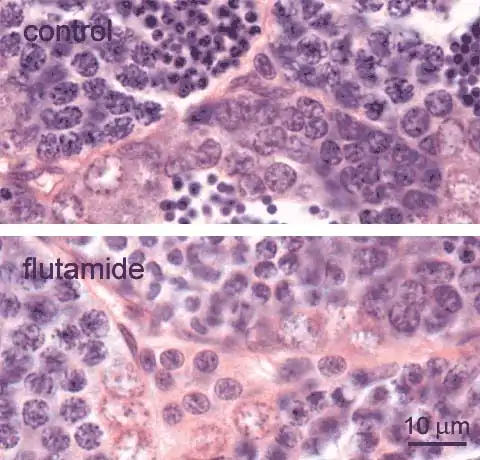

Leydig cells [outlined], also known as interstital cells, are found in the interstitial space between the testis tubules. These cells have regularly shaped round or oval nuclei. In the control testis, they occur solitairy or in small clusters; larger clusters are observed after exposure to the anti-androgen flutamide, shown here [lower image] for comparison. Occasionally, such larger clusters may also be present at the periphery of the control testis.

Note, that apart from Leydig cells, other cells [arrowheads], such as fibroblasts and smooth muscle cells, are also present in the interstitium.

Adult male zebrafish, control (top), and exposed to 1 mg flutamide /L (bottom); H&E staining |